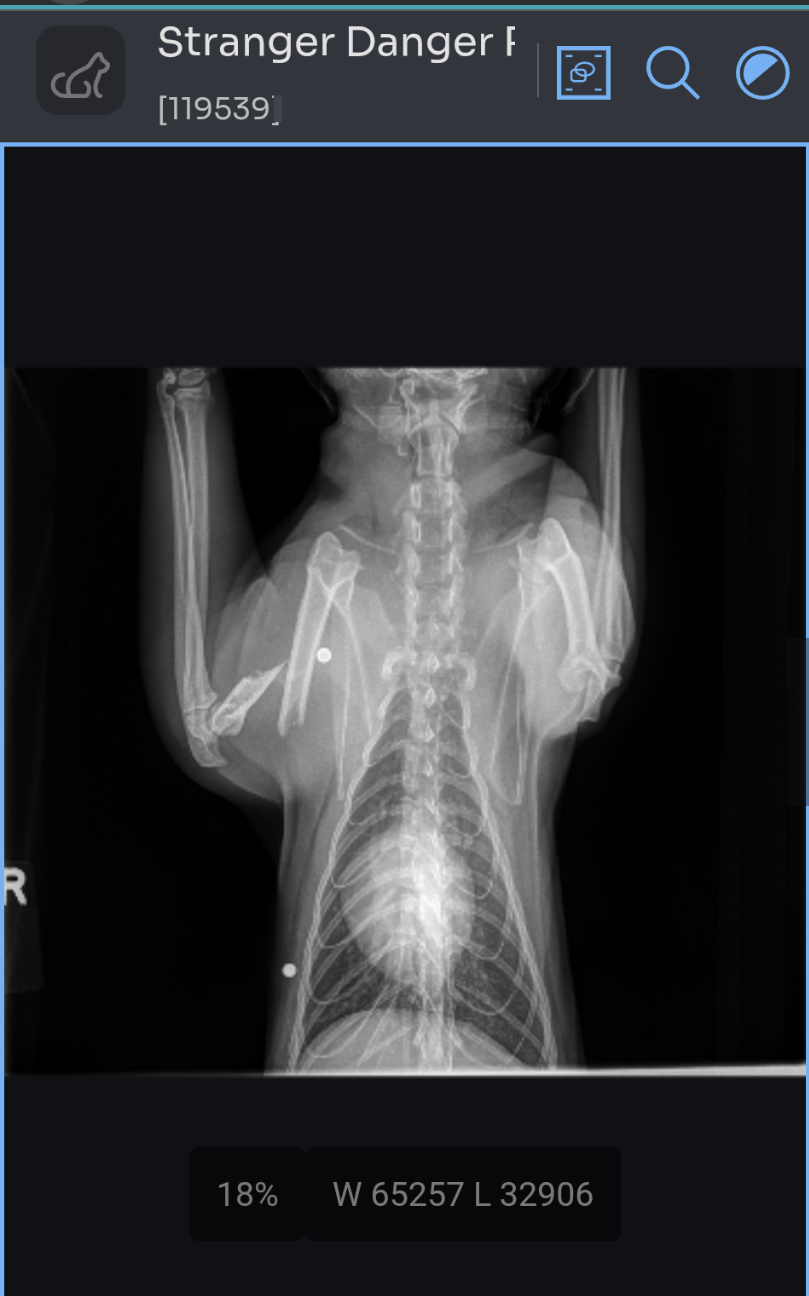

They prescribed painkillers so that we could bring him to our primary care vet the next day to diagnose with X-Rays. The X-Rays revealed that Stranger had been shot twice with a pellet gun. One of the pellets completely broke his humerus (upper arm bone). The extremely professional and helpful veterinarians at Desert Sky Animal Hospital indicated to us that amputation was an option, but strongly encouraged us to consult with an Orthopedic specialist.